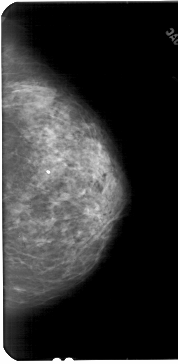

A_1842_1.RIGHT_MLO

RIGHT_CC LINES 5446 PIXELS_PER_LINE 2656 BITS_PER_PIXEL 12 RESOLUTION 43.5 NON_OVERLAY